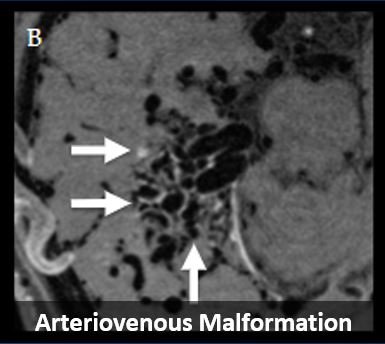

Vessel Wall MR Imaging of Aortic Arch, Cervical Carotid and Intracranial Arteries in Patients with Embolic Stroke of Undetermined Source (July 2022)

We review intracranial, carotid, and aortic vessel wall MR imaging techniques used to identify culprit plaque in patients with ESUS. View animated visual abstract here.

Imaging Biomarkers & Prevalence of Complex Aortic Plaque in Cryptogenic Stroke (Nov 2023)

We review imaging features by imaging modality (TEE, CT/CTA, MR/MRA) of complex aortic plaque. The prevalence of complex aortic plaque is also calculated in patients with embolic stroke of undetermined source. See twitter teaser here.

MRI in the Evaluation of Cryptogenic Stroke and Embolic Stroke of Undetermined Source (Apr 2024)

We review the diagnostic utility of various MRI techniques in patients with cryptogenic stroke.